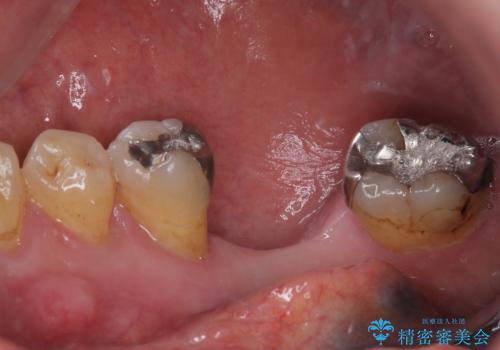

- 奥歯を抜歯してから放置しているとのことで来院された患者様です。

歯が割れて抜歯になってしまったとのことで、咬合力に抵抗できるよう、インプラントによる補綴治療を行うこととしました。

むし歯の放置期間と抜歯してからの放置期間が長く、咬み合わせる上顎の歯がやや伸び出している状態でした。

上顎の部分矯正や対合歯の補綴治療も提案しましたが、今回は欠損部のみの治療を行いました。